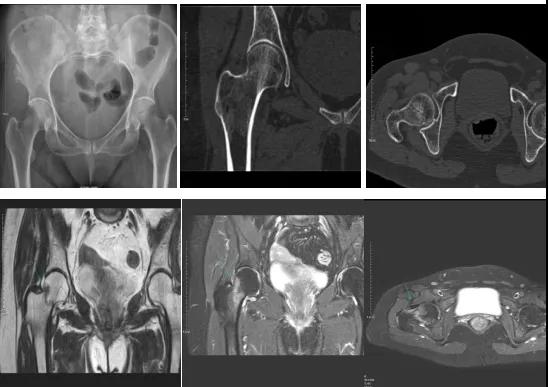

2.CT或MRI檢查。CT是斷面成像,不會(huì)出現(xiàn)重疊而導(dǎo)致漏診,同時(shí)CT還可以進(jìn)行多平面的重建,除了發(fā)現(xiàn)X線無(wú)法發(fā)現(xiàn)的骨折外,還可以三維直觀的顯示骨折的程度,對(duì)臨床治療有指導(dǎo)意義。CT無(wú)法發(fā)現(xiàn)骨裂、不全骨折或者骨挫傷,對(duì)軟組織的損傷診斷也有局限性,MRI就可以發(fā)現(xiàn)這些損傷。

DR示:右側(cè)股骨頸未見明顯骨折征象。CT右側(cè)股骨頸骨質(zhì)密度不均?;颊唧w征明顯,為明確診斷,行MRI檢查。MRI示:右側(cè)股骨頸T1WI呈低信號(hào),脂肪抑制序列呈高信號(hào);提示右側(cè)股骨頸隱匿性骨折。